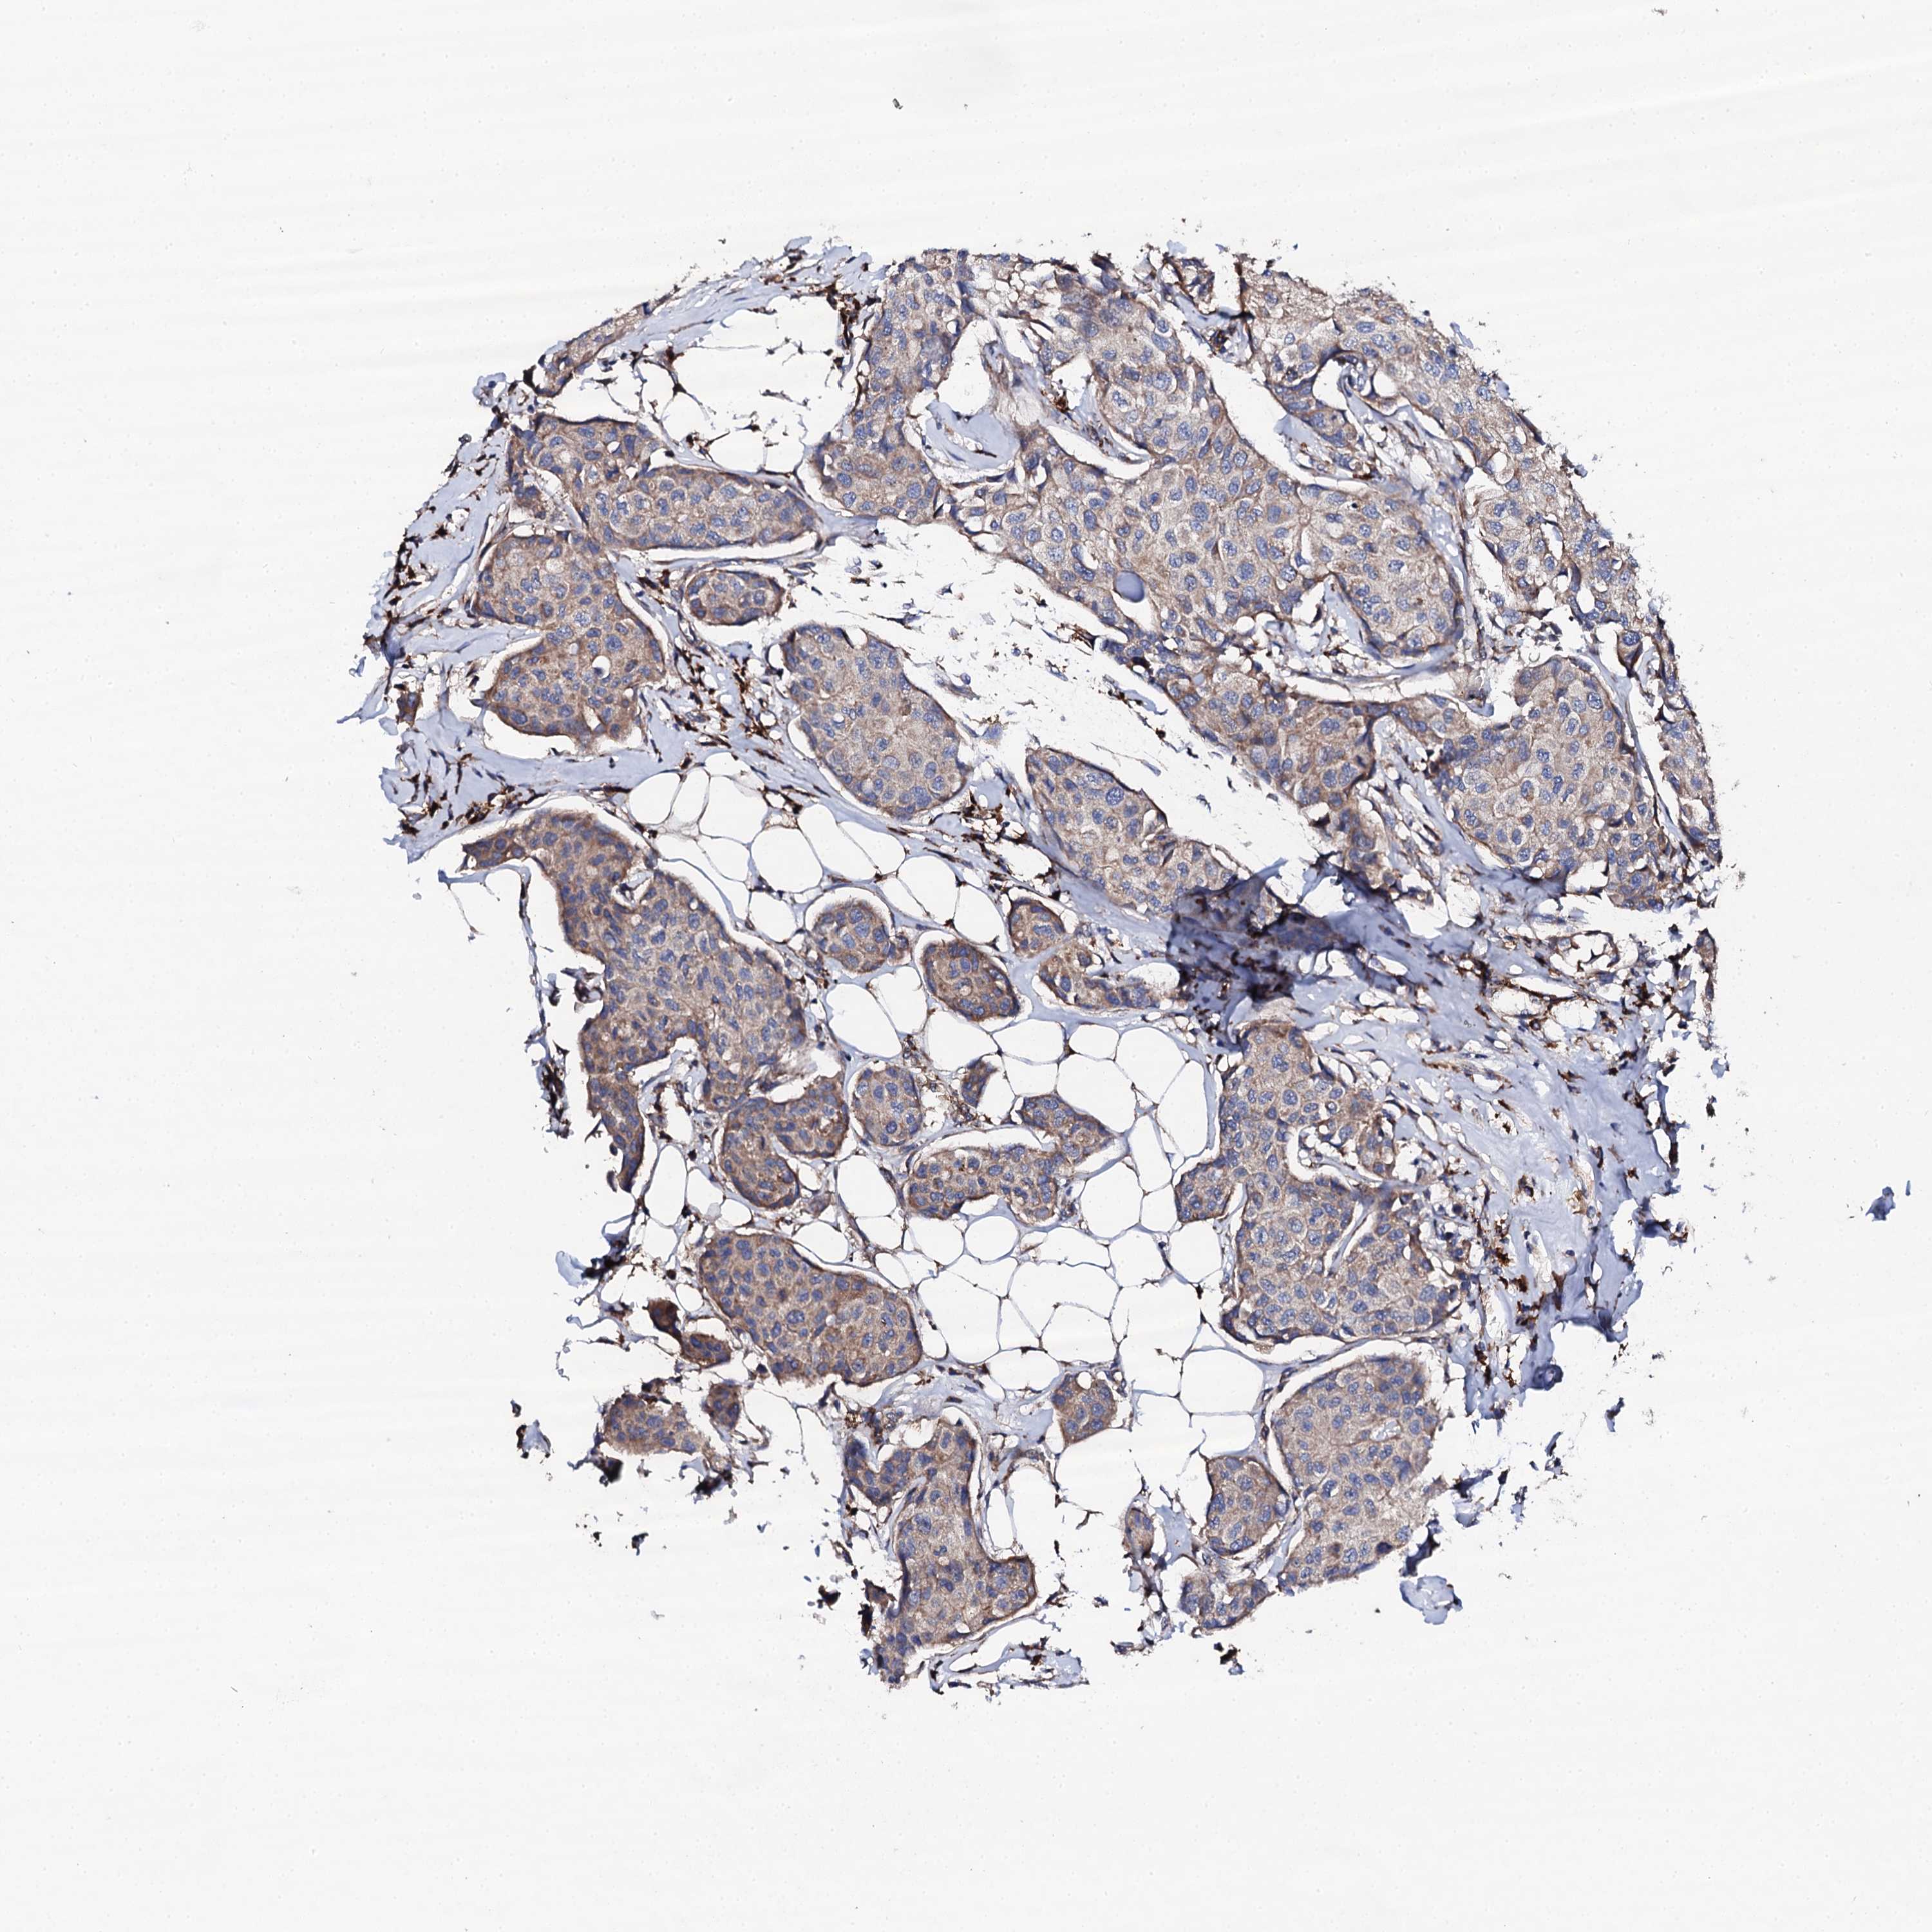

CANCER BREAST CANCER Show tissue menu

BRCA TCGA BRCA VALIDATION PROTEIN EXPRESSION